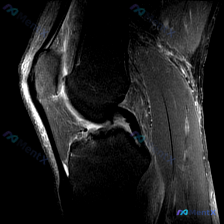

这是一张膝关节矢状位T2加权MRI单层面图像,临床提示观察「软骨异常」。

影像客观所见

先给大家列全所有阳性和阴性发现:

- 韧带:后交叉韧带、前交叉韧带连续性都好,走行自然,没有断裂、中断,也没有异常高信号

- 骨结构:股骨、胫骨骨髓信号均匀,没有异常斑片信号,关节面骨皮质连续,没有骨赘、骨质侵蚀

- 关节积液:髌股关节间隙和髌上囊可见中等量高信号液体影,明确存在关节内积液

- 髌下脂肪垫:信号正常,没有弥漫增高也没有软组织肿块

- 软骨:髌骨后方、胫股关节面软骨没有明显局灶性缺失、严重变薄,没有看到明确的典型软骨损伤征象

看到这个结果,第一反应其实是:临床说要找软骨异常,但客观影像上软骨没问题,核心阳性发现其实是孤立性关节积液,得把分析起点调整对,别被「软骨异常」带偏了。